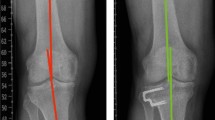

Radiological measurements are illustrated in Fig. 1. The KJLO was defined by the medial proximal tibial angle (MPTA), which is the medial angle between the line tangential to the tibial plateau surface and the tibial mechanical axis [37]. Medial joint space width (mJSW) was measured by the minimum interbone distance between the medial tibial plateau and the medial femoral condyle [39]. HKA was measured by the angle between the femoral mechanical axis and the tibial mechanical axis [6]. The mLDFA was measured by the lateral angle between the tangential line of the femoral condyles and the femoral mechanical axis [32]. Joint line convergence angle (JLCA) was measured by the angle between the tangential line of the femoral condyles and the tangential line of the tibial plateau [32]. Wedge size was obtained by targeting the lower limb mechanical axis at one-third of the lateral knee compartment (4° valgus HKA). The Kellgren and Lawrence (KL) classification was used to grade knee osteoarthritis severity, with four ordinal grades: 1 (doubtful), 2 (mild), 3 (moderate), 4 (severe) [18, 23]. The mJSW and the KL grade progression (≥ 1) were used to evaluate radiological progression of medial knee osteoarthritis [8].

Anteroposterior double-leg standing radiographs were used to assess MPTA, HKA, mLDFA, JLCA, and wedge size, and anteroposterior short knee standing radiographs were used to assess mJSW and KL grade. Patients were positioned with full knee extension and patellar forward during filming. Preoperative and postoperative MPTA, preoperative and postoperative mLDFA, preoperative and postoperative JLCA, and postoperative HKA were measured (TX), and their reliabilities were assessed by two observers (TX, RWB) in 40 patient cases from that patient database, with a three-week interval. The intra-observer and the inter-observer intra-class correlation coefficients of MPTA, mLDFA, JLCA, and HKA were at least good (> 0.75) [24, 48]. Preoperative HKA and wedge size were obtained during planning of lateral closing-wedge HTO (MH). The preoperative and the postoperative mJSW and KL grade were obtained by two orthopedic surgeons who were blinded to the patient’s clinical status using paired reading and sequence-known method [13]. The picture archiving and communication system (Philips Vue, N.V.) was used for radiological measurement, with a minimal determination of 0.01° angle and 0.1 mm distance.